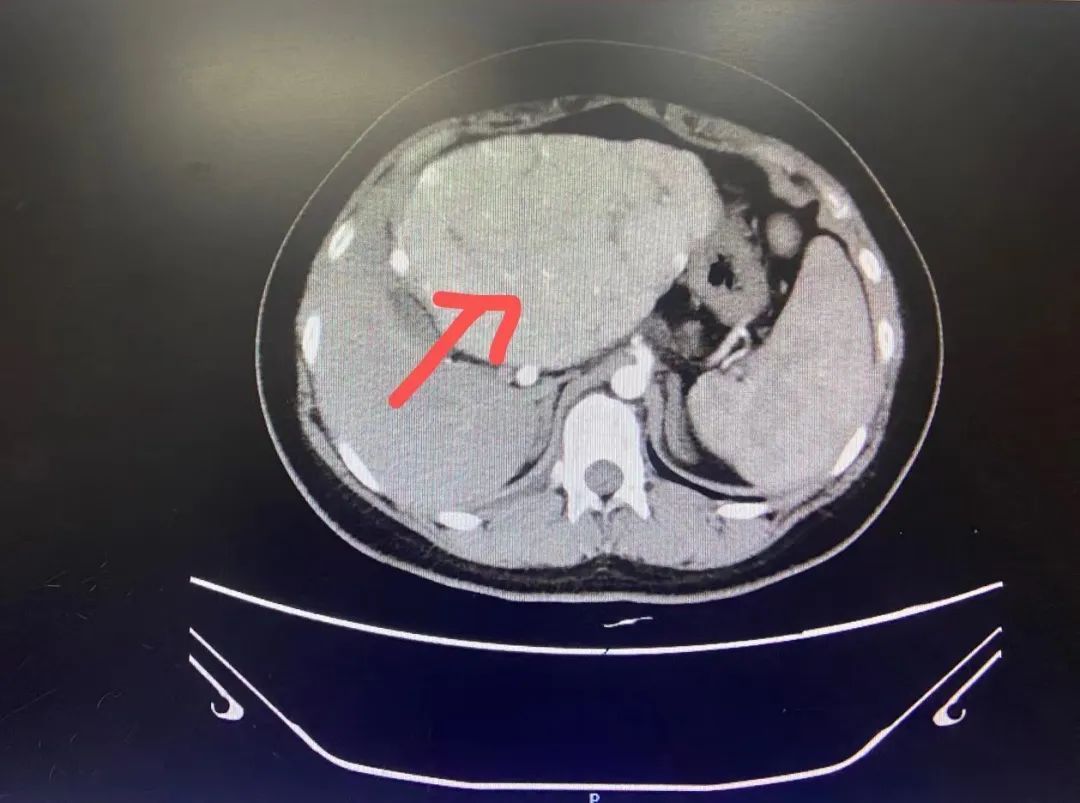

小雅近日因肝功异常来到我院消化内科就诊,没想到,经过一番检查之后,结果令全家人都颇为震惊,她被确诊为纤维板层样肝细胞肝癌。 据了解,小雅是一名正在读高三的女生,尽管平时学习压力大,但在父母的精心照顾以及自身注重劳逸结合的情况下,身体素质还算不错,学习成绩也相当优异,对于未来有着美好的憧憬和抱负。然而,一切转折就发生在高考体检期间,小雅被查出肝功异常。 医生询问小雅病史时得知,小雅家族中无肝炎病史,平时更是滴酒不沾,除了平时挑灯夜战刻苦学习之外,无任何不良嗜好,平时没有任何腹痛、腹胀、恶心、呕吐、易疲劳等不适,针对肝功异常,再次复查肝功提示转氨酶仍轻度偏高,完善肝胆胰脾彩超提示肝脏左叶异常回声包块。进一步检查肝炎系列、自免肝均未见异常,检查上腹部增强CT提示:肝左叶占位性病变,纤维板层样肝细胞肝癌可能(如图1、图2)。所幸发现较早,现在小雅已被转诊至外科进一步治疗。 大家一定很好奇,为什么年纪轻轻怎么会患癌?纤维板层样肝细胞肝癌又是什么病?

肝脏增强CT扫描图 纤维板层型肝癌(fibrolamellar carci-noma of liver,FLC)是肝细胞癌(Hepatocellular carcinoma,HCC)的一种特殊类型,在我国、日本及普通型肝细胞癌多发的地区罕见,其临床、病理、预后均区别于普通型肝细胞癌。 1.临床特点:该型癌有如下特征:①青年人多见,女多于男(1.07:1);②血清HBV标志物多阴性;③血清AFP阴性;④不伴肝硬变;⑤肿瘤常为单个,多位于肝左叶,瘤体内可有钙化灶;分化程度好,生长缓慢;⑦切除后生存期长,平均32~68个月。该型肝癌在我国少见,在肝癌低发的某些西方国家多见。 2.临床表现:多见于儿童及青少年,多无肝炎及肝硬化病史,甲胎蛋白、乙肝表面抗原常为阴性,肿瘤发现时体积常超过10cm,CT常能发现瘤灶中心瘢痕和钙化灶。肿瘤大多为单个实性结节,以癌细胞巢间出现大量平行排列的板层状纤维组织及强嗜酸性颗粒状的癌细胞浆为其主要病理特点。FLC出现生长发育停滞及男性第二性征发育不良罕见。有学者研究发现FLC癌细胞中产生大量能将雄烯二酮和睾酮等雄激素转化为雌酮和雌二醇的芳香化酶。血中高雌二醇低睾酮水平可加速骨骺闭合,可能导致男性骨龄正常,但第二性征发育不良及身高低矮。 3.治疗及预后:手术切除是治疗FLC的主要办法,与普通型肝细胞癌相比,切除率高、预后好。FLC肿瘤生长缓慢,癌细胞分化较好、恶性程度较低。 隐忍的肝脏需格外关注 肝脏是人体重要的生化工厂和解毒器官,它的个性就是天生“隐忍”,肝脏上没有痛觉神经分布,所以不到万不得已是不吭声的。 肝脏有强大的代偿能力,即使肝细胞已经损害70%,人们也未必会察觉到不适。肝癌早期并没有明显的临床症状,或者就只是出现一些乏力、消化不良、厌食或腹胀等这些不典型的症状,这些症状我们平时都会碰到,所以容易忽视,这也是为什么肝癌一经发现就是晚期的重要原因。 所以日常生活中除了要避免吸烟饮酒、过度肥胖、长期熬夜、胡乱吃药、抑郁易怒、接触各种受血液污染的操作之外,更要注意定期体检,做到早发现、早诊断、早治疗。